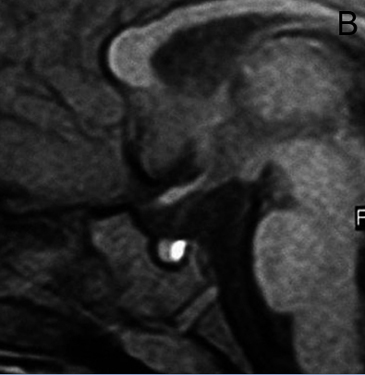

Figura 8. Corte sagital, secuencia T1w con Gadolinio, se observa un pequeño quiste de la pars intermedia (punta de flecha), inmediatamente inferior al tallo pituitario.